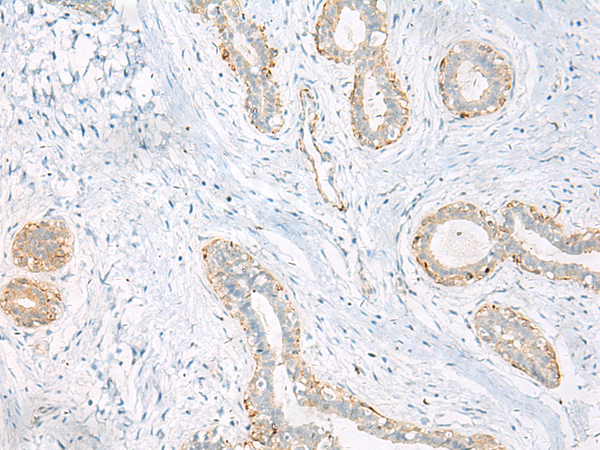

分类: 科研抗体货号: P11261别名: HGFR; AUTS9; RCCP2; c-Met应用: IHC反应种属: Human, Mouse, Rat